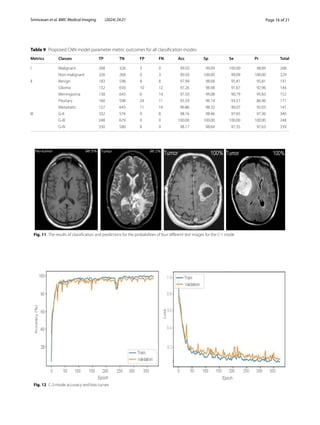

Figure 11 shows the results of the classification and

the predicted probabilities for each of the four tests

conducted in C-1 mode. Implementing the fivefold

accuracy and loss plots of the suggested CNN model for

the C-2 task are displayed in Fig. 12. The proposed CNN

method for the C-2 mode achieves a 93.81% accuracy in

classification after 294 iterations. As shown in Fig. 13, the

area under the ROC curve has a value of 0.9981. These

Fig. 11 The results of classification and predictions for the probabilities of four different test images for the C-1 mode

Fig. 12 C-2-mode accuracy and loss curves